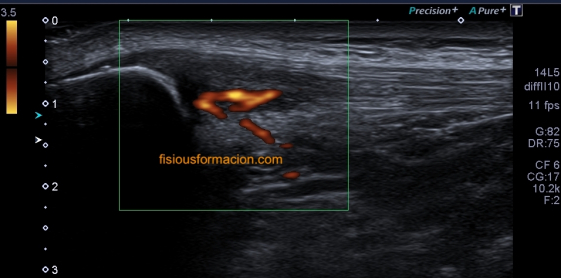

Una vez que tuve controlado el aspecto normal de músculo en la misma localización donde la paciente tenía el bulto, me dirigí a la región del bultoma y estudié la lesión, descrita con anterioridad, siguiendo el protocolo de actuación en caso de neoformaciones, control, medidas, doppler color y power y finalmente comparativa.

El estudio doppler arroja el hallazgo de un vaso importante que está alcanzando y nutriendo la región afectada. Puedes observar como es un vaso de alto flujo y de buen tamaño. No pude demostrar vascularización perimetral de la lesión.